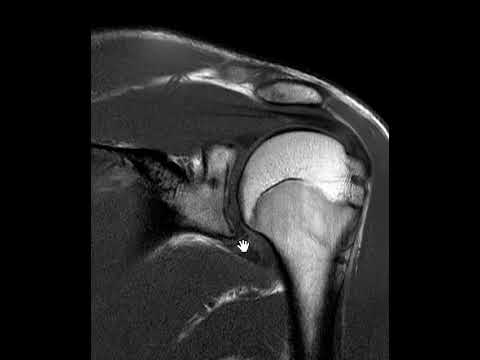

Как диагностировать передний и задний вывих плеча!

В этом видео я покажу вам, как отличить передний и задний вывих плеча. 🦴 Рентгенологические случаи: Случай 1: Случай 2: Случай 3: Случай 4: Случай 5: 🎥 Посмотрите другие мои недавние видео: Как интерпретировать рентгенограмму плеча! – • How To Critique a Shoulder X-Ray! Почему её называют «Y-латеральной»? – • Why is it called a ‘Y-Lateral’? Остеоартрит (ОА) против ревматоидного артрита (РА): всё понятно! (+ примеры рентгенограмм) – • Osteoarthritis (OA) vs Rheumatoid Arthriti... Остеопороз против остеопетроза: всё понятно! – • Osteoporosis vs Osteopetrosis: Explained! Переломы длинных трубчатых костей: всё понятно! (+ Примеры рентгеновских снимков) – • Long Bone Fractures: Explained! (+ X-Ray E... ⌚️ Тайм-коды: 0:00 — Вступление 0:20 — Рентгеновские снимки — это двумерные снимки 0:28 — Какие бывают проекции? 0:57 — Демонстрация 3D-анатомии 1:26 — Передний вывих — Механизм травмы 2:19 — Задний вывих — Механизм травмы 2:50 — Признаки вывиха 3:29 — Случай 1 4:25 — Случай 2 5:28 — Случай 3 6:27 — Случай 4 7:15 — Случай 5 8:21 — Видеообзор плечевого сустава 8:36 — Заключение 💬 Если вы хотите, чтобы я рассмотрел какую-то конкретную тему, напишите об этом в комментариях ниже. 📎 МОИ КЛЮЧЕВЫЕ ССЫЛКИ: 👔 LinkedIn - / sahand-hooshmand-phd-a72b97118 🐦 X - 🎓 Профиль USYD - 🥼 ResearchGate - 📝 Диссертация - 📰 Последняя публикация - КТО Я: Меня зовут Саханд, я преподаватель и рентгенолог (а теперь и ютубер?) из Сиднея, Австралийского университета. В 2023 году я получила докторскую степень (медицина и здоровье) по специальности «визуализация рака молочной железы и дозы облучения». Я постоянно учусь, мне всегда интересно, что происходит вокруг, и я здесь, чтобы снимать видео и делиться своим уникальным взглядом на концепции, которые могут вам понадобиться. 🔔 Подпишитесь, если хотите увидеть больше :)